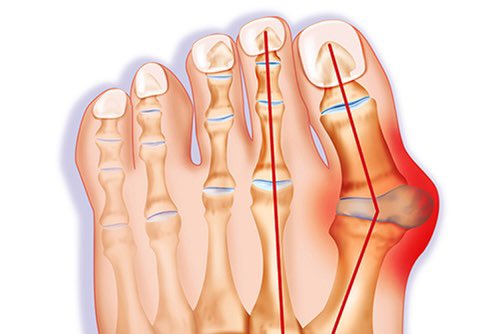

١-اتجاه إبهام القدم للداخل نحو الأصبع الثاني،وحدوث بروز عظمي من الجهة الأخرى(السلامية العظمية)

٢-نطاق الحركة في مفاصل إبهام القدم،والمفاصل المحيطة من ناحية القدم الوسطى

يراجع كثير من مرضى العظام وخصوصًا النساء العيادة يشكون انحرافًا واعوجاجًا في إبهام القدم الذي يسبب لهم ألمًا واحتكاكًا بالحذاء أثناء المشي تارةً، وتارةً يؤرقهم بسبب شكله، أولصعوبة لبس الحذاء.

سأتناول هنا انحراف إبهام القدم بتفاصيله...